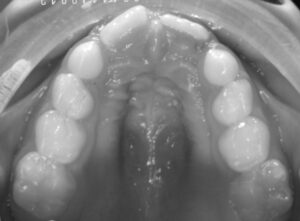

Hay que pensar que el suelo de las fosas nasales, es el techo de la cavidad oral ( el paladar). Un niño que no usa la nariz, ES UN RESPIRADOR ORAL respira por la boca) y presentará con el tiempo una nariz pequeña, poco desarrollada, narinas frontales y un paladar estrecho.

¿y porqué un paladar estrecho?

El desarrollo del maxilar superior depende :

- de la respiración nasal: el paso del flujo de aire nasal

- y de una buena posición de reposo de la lengua, cuyo dorso ha de estar apoyado en el paladar. Cuando un niño respira por la boca y no usa la nariz, para poder llevar esa respiración oral la lengua está en posición baja, no apoya su dorso contra el paladar ( en la respiración nasal sí) y por eso se ve afectado su desarrollo transversal.

- el paladar se queda estrecho por el NO uso de la nariz, y porque la lengua, cuyo dorso tendría que apoyarse en el paladar ( otro de los factores que inducen a un buen desarrollo del maxilar superior) se queda en una posición baja para permitir esa respiración oral, por lo tanto el maxilar no se desarrolla bien, se queda estrecho y por mucho que le digamos dónde ha de colocar la lengua, no lo hará porque ya no cabe en ese paladar .